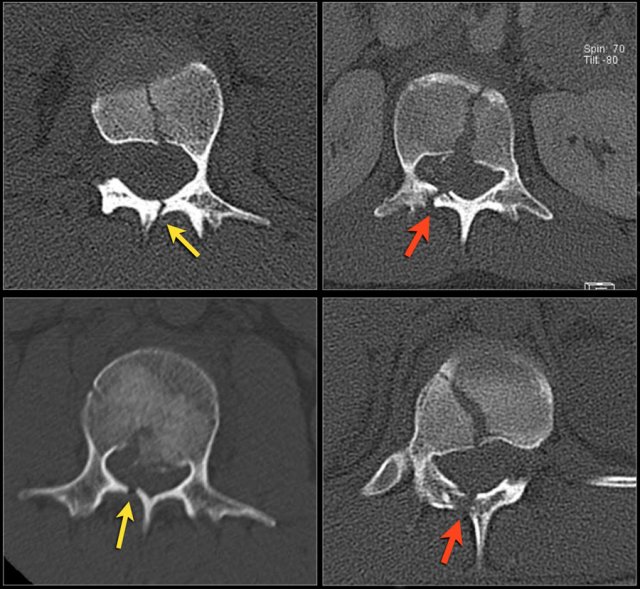

The findings are:

1. The main feature is posterior distraction with horizontal fractures of posterior elements (red arrow)

2. Avulsion of a spinous process (yellow arrow)

3. Widening of facet joint (green arrow)

4. Burst-type fracture

In this case some would call this a burst fracture with PLC-injury i.e. 2+3 points.

However the distraction is the most important finding, i.e. distraction and PLC injury, i.e. 4+3 points.